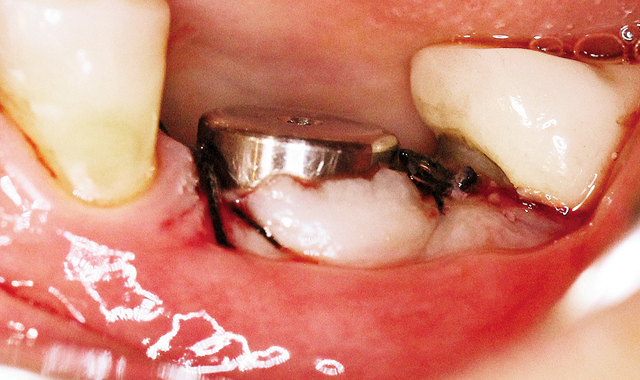

Fig. 3 WIDE PLATFORM TAPERED TITE FIT 5 mm implant (HI-TEC IMPLANTS)

In order to achieve the required result, a WIDE PLATFORM TAPERED TITE FIT 5 mm implant (HI-TEC IMPLANTS) was selected (Fig. 3).